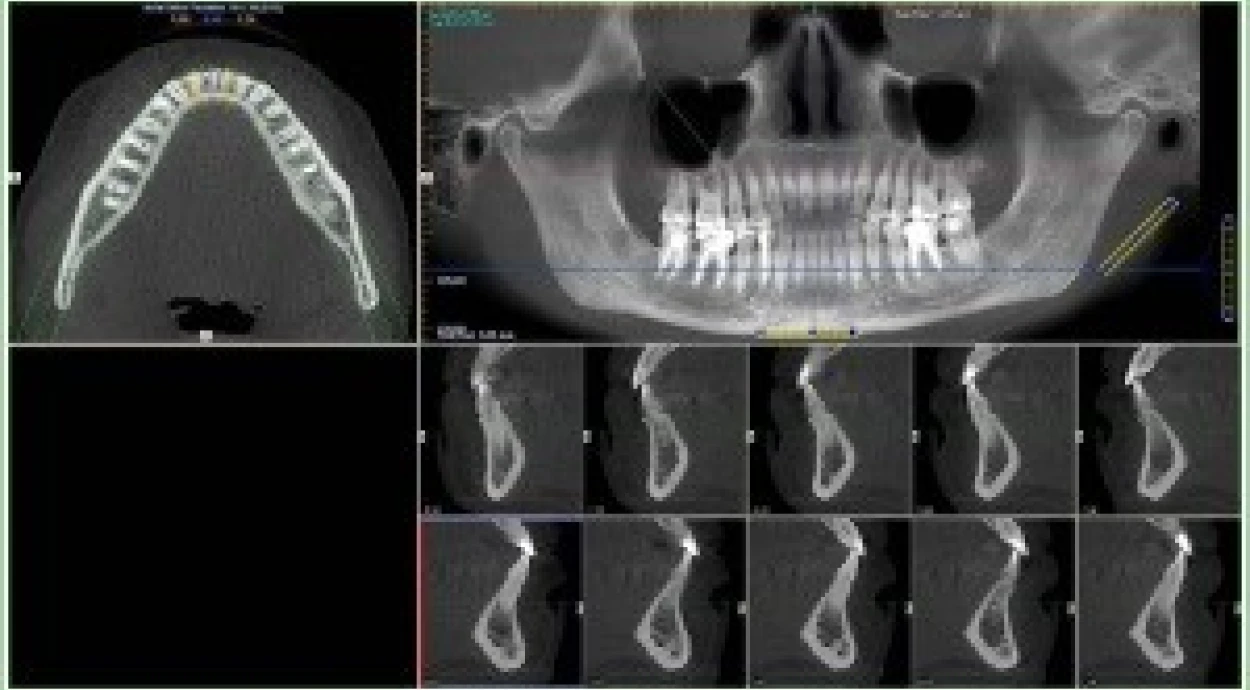

Диагностика в области стоматологического здоровья выходит на качественно новый уровень. Пациенты «Оксфорд Медикал» теперь имеют возможность воспользоваться новым цифровым панорамным рентгенаппаратом VATECH PaX-Uni3D с функцией КТ (компьютерной томографии). Преимуществом данного аппарата является возможность локального обследования критических зон при минимальном облучении пациента. Всего за несколько секунд происходит захват изображения по всей области сканирования. При этом пациент может самостоятельно координировать свое положение благодаря «подсказкам» на встроенном TFT дисплее.

В отличие от классической рентгенодиагностики, дентальный компьютерный томограф обладает функцией создания трехмерного изображения проблемного участка полости рта. Процесс съемки полностью компьютеризирован. Сканирование осуществляется благодаря встроенной видеокамере, а также системе позиционирования пациента. Далее специальная программа приступает к анализу полученных 3D реконструкций костной ткани. Таким образом, специалисты имеют возможность исследовать отсканированный участок на любом слое, отследить изменение толщины и плотности тканей, а также смоделировать оптимальную постановку имплантата. Кроме того, функциональные параметры аппарата позволяют выполнять снимки в различных проекциях (панорамная, фронтальная, снимок верхнечелюстных пазух). Программы повышения четкости изображения критических зон дают возможность выявить широкий спектр стоматологических проблем, таких как пародонтоз, кариес, наличие пломбированных корневых каналов и др. Технические параметры аппарата предусматривают наличие анатомических программ. Например, по типу (взрослый мужчина, взрослая женщина, ребенок) или телосложению (нормальное, худое, тучное).

VATECH PaX-Uni3D имеет функцию цефалометрического анализа (оценки размеров и пространственного взаимоотношения зубов, челюстей и лицевого черепа в целом), благодаря чему квалифицированные специалисты нашей клиники могут изучить алгоритм роста каждого элемента зубочелюстной системы и предотвратить возможное появление нарушений в будущем.

Упомянутые характеристики гарантируют исключительно точное определение природы заболевания, способствуют установлению правильного диагноза, а также согласованию дальнейших лечебных мероприятий.